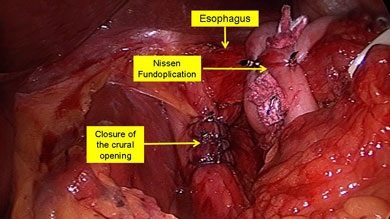

Scopul interventiei chirurgicale este de a restabili bariera antireflux, fără a crea obstacole în calea bolului. Nissen fundoplicatură - chirurgie antireflux, în care folie gastric în jurul părții inferioare a esofagului 360 °. creând o manșetă care previne conținutul gastric în esofag. Inainte de operatie, pacientii ar trebui sa fie examinate cu atenție, o atenție deosebită trebuie acordată la ultimul etaj al radiografiei tractului gastro-intestinal pentru a exclude alte posibile boli.

Principalele etape ale fundoplicatură Nissen:

- creând un drum liber Nissen înălțime manșetă de 1 - 2 cm;

- fixarea manșeta la esofag și piciorul drept al diafragmei;

- excizia sacul herniei și suturarea diafragmei la picioarele HH.

Manșetă Nissen reticulat pe două rânduri sutura.

Creați gratuit înălțimea Manșetă Nissen de 1 - 2 cm